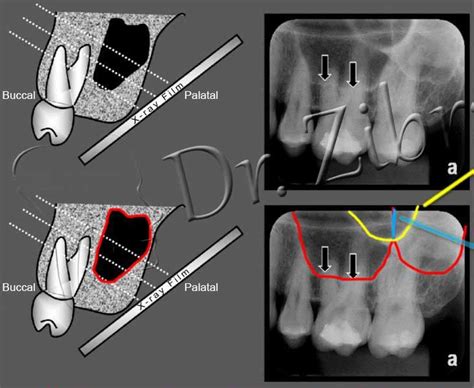

Endo Access With Upper Premolar With Two Canals